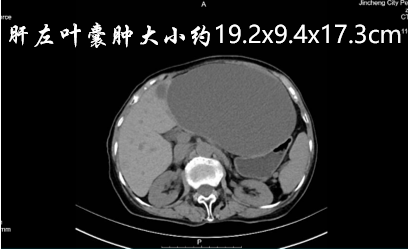

通过CT检查,医生发现张奶奶肝左叶的囊肿大小约19.2x9.4x17.3cm,足足有一个排球那么大。这个 “大水囊” 不断压迫着周围脏器,正是导致她腹痛、腹胀的根源。更棘手的是,张奶奶年事已高,免疫力偏低(检查显示白细胞计数、淋巴细胞绝对值均低于正常范围),且对传统开腹手术充满恐惧,手术意愿低。如何在保证安全的前提下,用最小的创伤为老人解除病痛,成为科室团队亟待解决的难题。